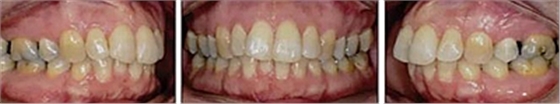

患者曾行正畸治療,現(xiàn)覺笑容不美觀前來就診。患者正面觀及側(cè)貌示下頜發(fā)育不足,偏高角,唇閉合不全。上下頜中線齊。覆合、覆蓋4毫米。磨牙關(guān)系及尖牙關(guān)系II類。上頜擁擠度4mm,下頜擁擠度6mm。4顆第一前磨牙在第一次正畸治療時已拔除。上下牙弓呈尖圓型,牙弓狹窄。

頭影測量分析,SNA角84°,ANB角6°,高角型,詳見下表。